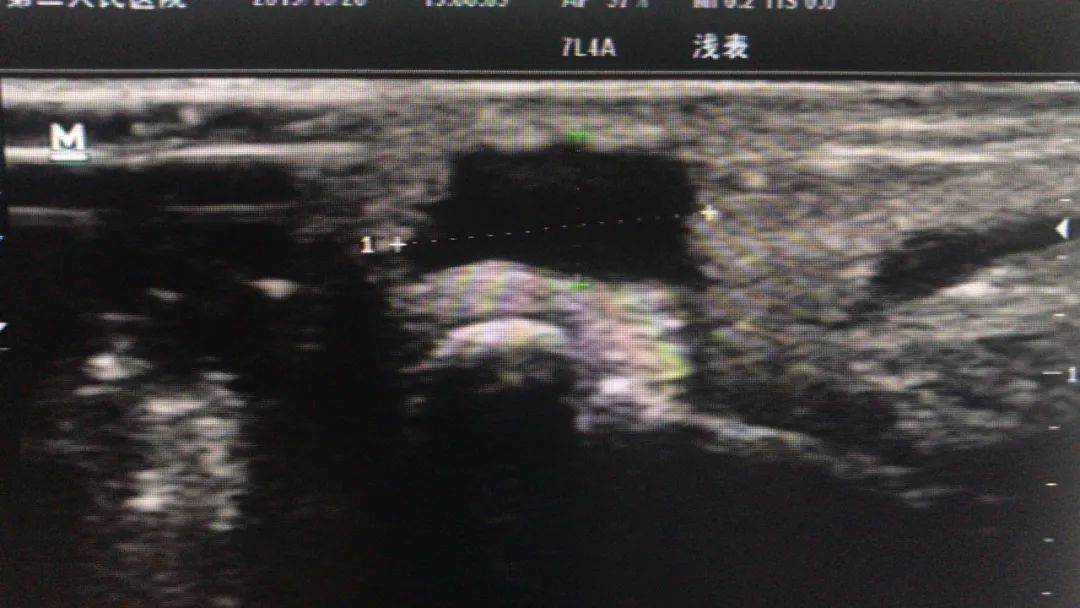

左图为手术前,右图为术后半年复发,比原来更大的囊肿